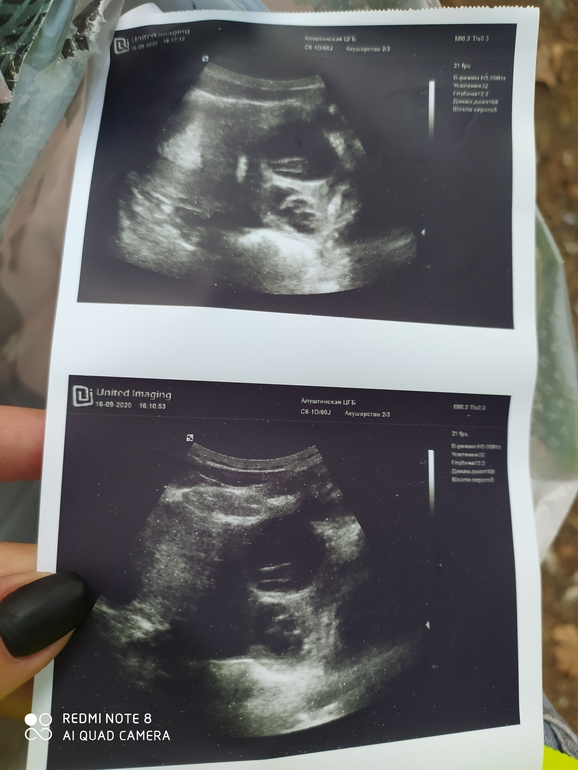

Это фолликулометрия на 15 дц

На 15 дц по УЗИ 2 фолика ,20 мм и 37 ,37 явно это и есть моя киста,а 20 мм где ??Лопнул и от него жидкость?

О не подтверждена,последнее УЗИ было на 15 дц , ПЯ-2 фолика 20 мм и 37

ЛЯ -2 фолика 10 мм и 13

37 мм явно перерос в кисту ,но куда делся 20 мм ???Тоже перерос или лопнул,может ли киста закрыть обзор жт ??